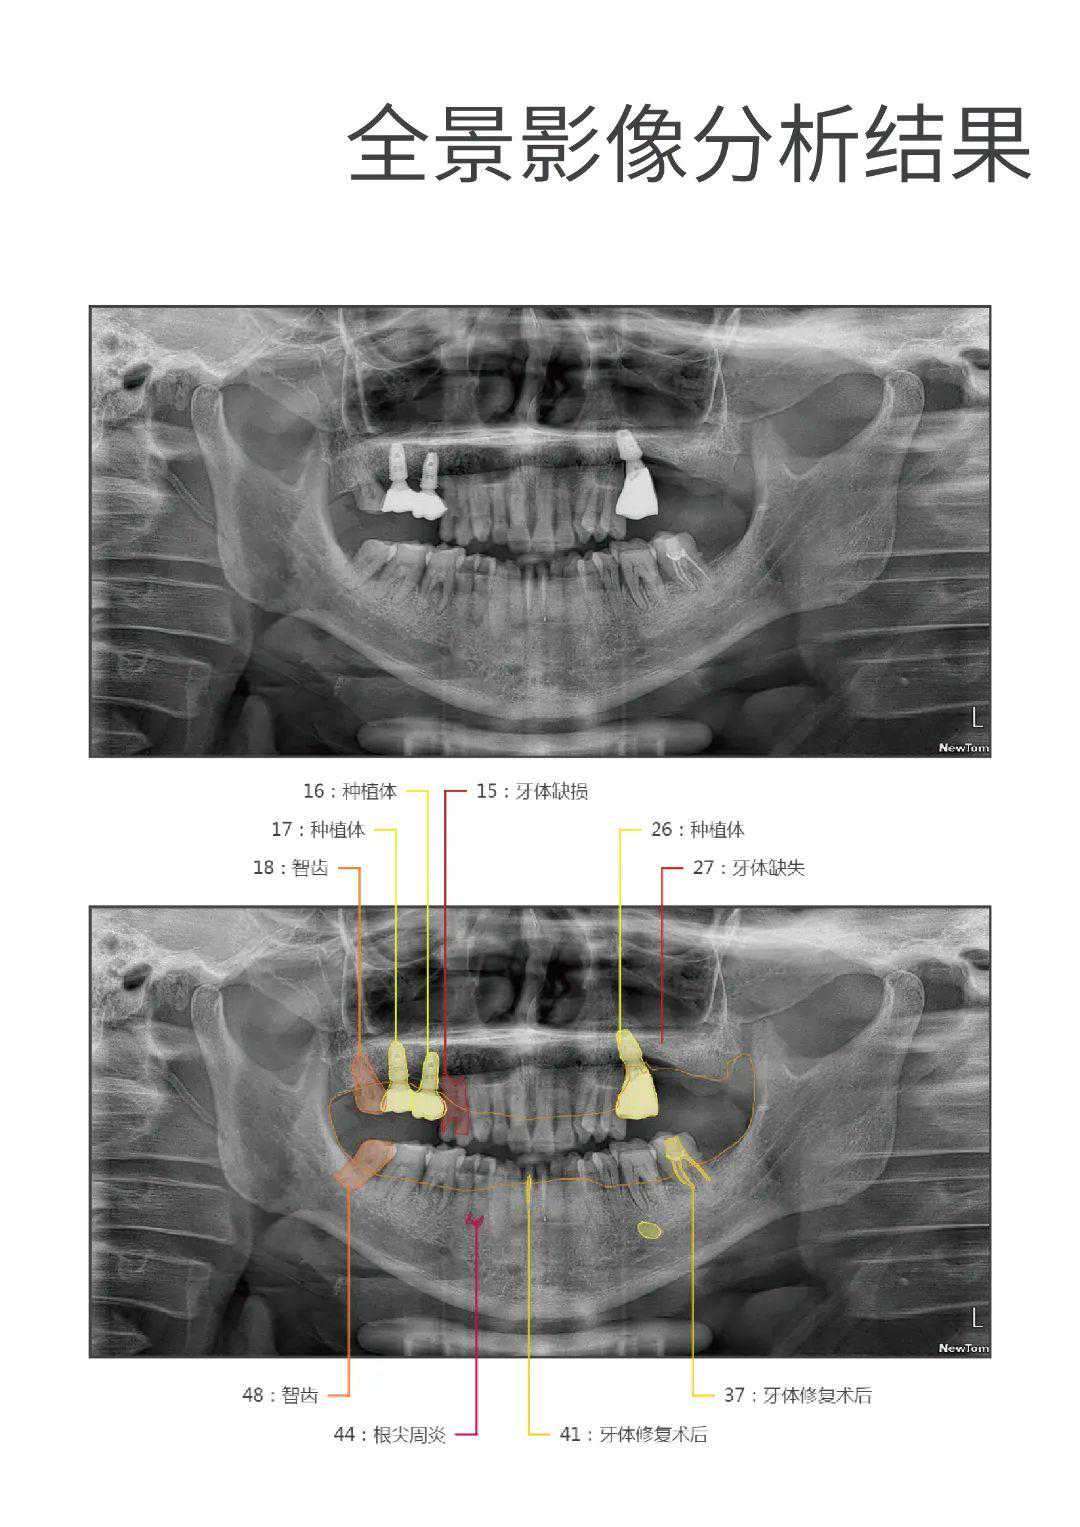

♥现在报名申领,可体验AI智能健康评估:

精准检测龋病、牙周炎、智齿、颌骨占位等23项口腔问题,模拟未来10年口腔变化等情况,生成十几页的详细检查报告,及时预防口腔疾病。

附口腔检查报告↓↓↓